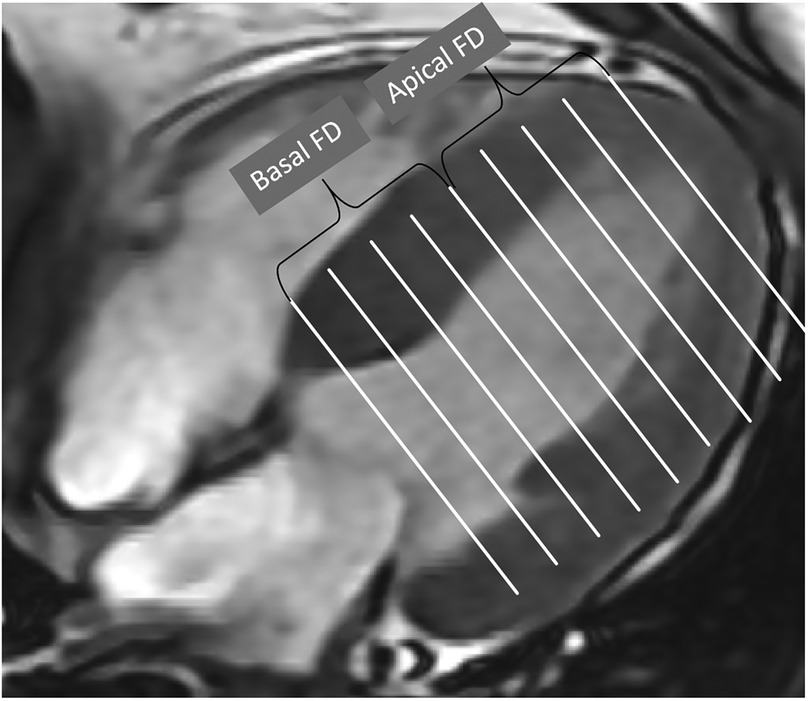

Fractal analysis of left ventricular trabeculae in hypertensive patients with heart failure: a 3.0 T cardiac magnetic resonance study

Abstract Background: Endocardial trabecular hyperplasia due to hemodynamic stress reflects phenotypic variability in disease progression. Employing fractal analysis, this study quantified left ventricular (LV) myocardial trabecular complexity in hypertensive patients with and without heart failure (HF) to evaluate its diagnostic utility for HF. Methods: This study retrospectively enrolled 146 hypertensive patients (77 with HF, 69 without), grouped into HTN-HF (n=77) and HTN non-HF (n=69); additionally, 34 healthy controls were recruited. Clinical data and cardiac MRI parameters were compared. Fractal dimension (FD) values were calculated on the LV short-axis cine images using fractal analysis. Logistic regression analysis was performed to determine predictors. Results: